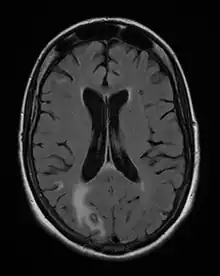

Acute toxoplasmosis is often asymptomatic in healthy adults.[13][14] However, symptoms may manifest and are often influenza-like: swollen lymph nodes, headaches, fever, and fatigue,[15] or muscle aches and pains that last for a month or more. It is rare for a human with a fully functioning immune system to develop severe symptoms following infection. People with weakened immune systems are likely to experience headache, confusion, poor coordination, seizures, lung problems that may resemble tuberculosis or Pneumocystis jiroveci pneumonia (a common opportunistic infection that occurs in people with AIDS), or chorioretinitis caused by severe inflammation of the retina (ocular toxoplasmosis).[15] Young children and immunocompromised people, such as those with HIV/AIDS, those taking certain types of chemotherapy, or those who have recently received an organ transplant, may develop severe toxoplasmosis. This can cause damage to the brain (encephalitis) or the eyes (necrotizing retinochoroiditis).[16] Infants infected via placental transmission may be born with either of these problems, or with nasal malformations, although these complications are rare in newborns. The toxoplasmic trophozoites causing acute toxoplasmosis are referred to as tachyzoites, and are typically found in various tissues and body fluids, but rarely in blood or cerebrospinal fluid.[17]

Due to the absence of obvious symptoms,[13][14] hosts easily become infected with T. gondii and develop toxoplasmosis without knowing it. Although mild, flu-like symptoms occasionally occur during the first few weeks following exposure, infection with T. gondii produces no readily observable symptoms in healthy human adults.[7][20] In most immunocompetent people, the infection enters a latent phase, during which only bradyzoites (in tissue cysts) are present;[21] these tissue cysts and even lesions can occur in the retinas, alveolar lining of the lungs (where an acute infection may mimic a Pneumocystis jirovecii infection), heart, skeletal muscle, and the central nervous system (CNS), including the brain.[22] Cysts form in the CNS (brain tissue) upon infection with T. gondii and persist for the lifetime of the host.[23] Most infants who are infected while in the womb have no symptoms at birth, but may develop symptoms later in life.[24]

The seroprevalence of T. gondii in humans varies between 10 and 70% worldwide, depending on the region and increases significantly with age. Upon infection, the parasites persist as intraneuronal cysts in the central nervous system (CNS) for the lifetime of the host (1, Figure 1). Until recently, parasite persistence in healthy individuals was regarded as clinically asymptomatic. However, in the last decade, several reports have indicated that chronic cerebral toxoplasmosis may impact on the behaviour of its host (2).